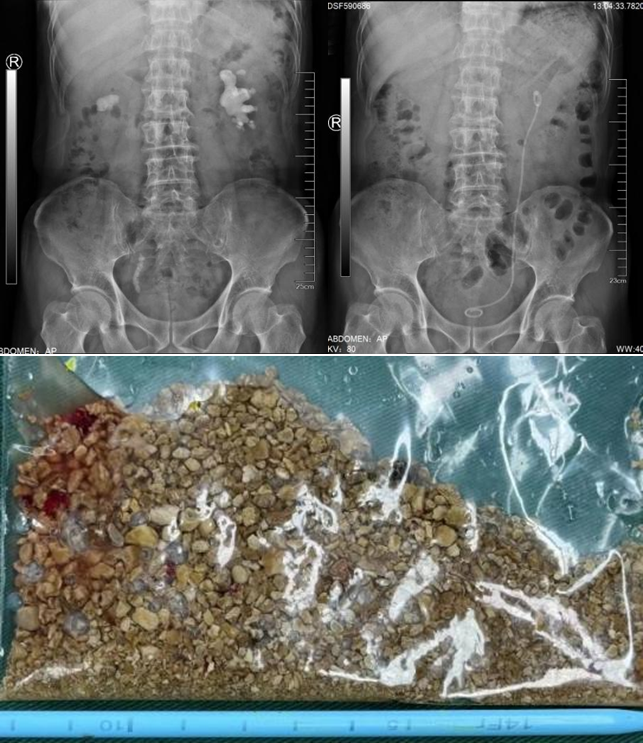

该例患者2年来出现右腰部反复疼痛,伴尿频尿急尿痛、肉眼血尿。来我院前曾经在外院检查B超提示右肾结石,选择进行保守治疗并定期复查。近期患者再发右腰部疼痛来我院就诊,B超检查提示:右肾结石,右肾囊肿。尿常规检查提示:白细胞:1332/ul,予以口服抗生素治疗1周后收住入院。入院后进一步完善相关检查,CT检查提示:右肾结石,大小约3.1x1.8cm,右肾囊肿大小约5.0x3.5cm,复查尿常规:白细胞:191/ul。浦金贤主任带领科室成员仔细阅片后指出,患者结石位于肾盂输尿管连接处,负荷较大,且尿常规检查显示白细胞较高,考虑结石伴发感染可能性大,需严格控制感染,术中应注意肾盂内压力,减少术后严重感染风险。同时,患者右肾囊肿体积较大,可以考虑同次手术一并处理。根据患者病情特点,周守军主任采用腹腔镜微创手术的方式,一期手术同时行腹腔镜肾盂切开取石和腹腔镜肾囊肿去顶术,将结石完整取出、肾囊肿去顶减压,一次手术解决两个问题。患者术后迅速康复,未出现发热、尿瘘等并发症,顺利出院。